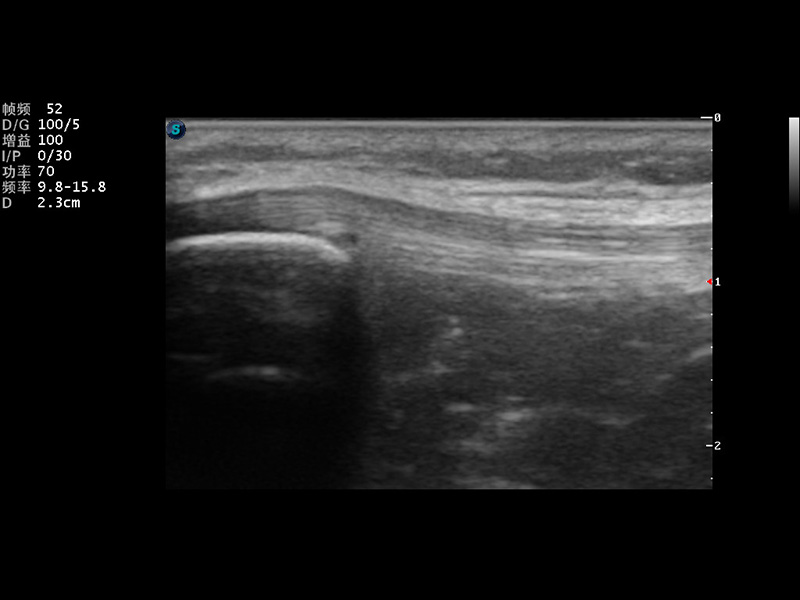

实时宽景成像